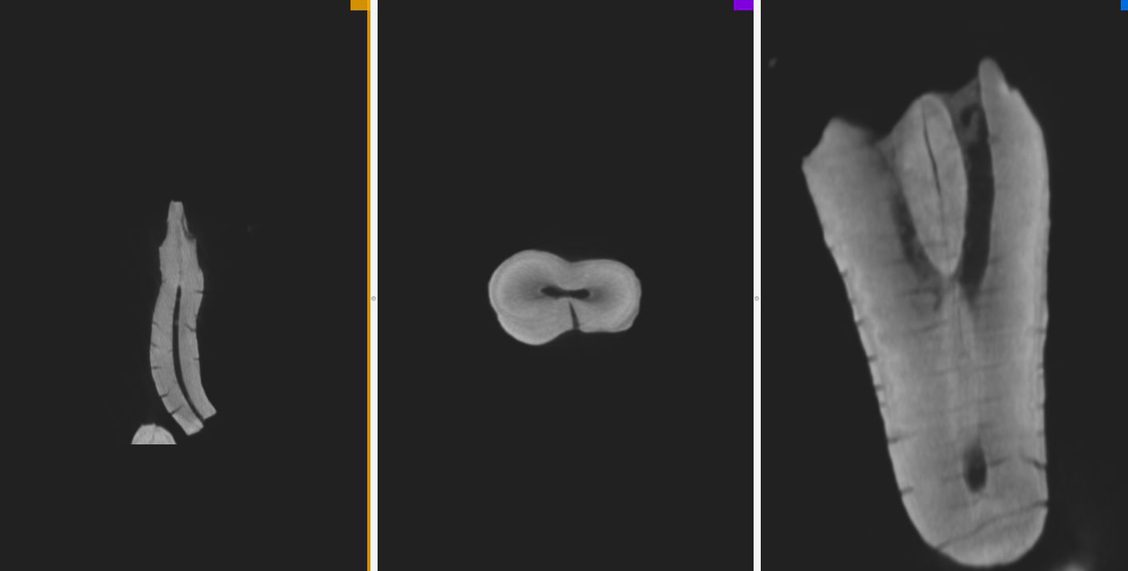

“Paleoradiology meets Archeology” je kongres koji svake dvije godine organiziraju Hrvatsko društvo za medicinsku antropologiju i Institut za arheologiju na kojem sudjeluju paleoradiolozi i antropolozi a i drugi stručnjaci koji koriste radiološke tehnike u humanističkim istraživanjima.

Kongres se obično naslanja na paleoradiološku radionicu a ove godine imamo 8 pozvanih predavača iz više zemalja. Hrvatska je na mapi paleoradiologije od 1901. kada je Gorjanović Kramberger snimio fosilne ostatke Krapinskog pračovjeka u bolnici Sestara milosrdnica u Zagrebu te od tada prati sve trendove u ovoj zanimljivoj ali široj javnosti još dosta nepoznatoj struci.